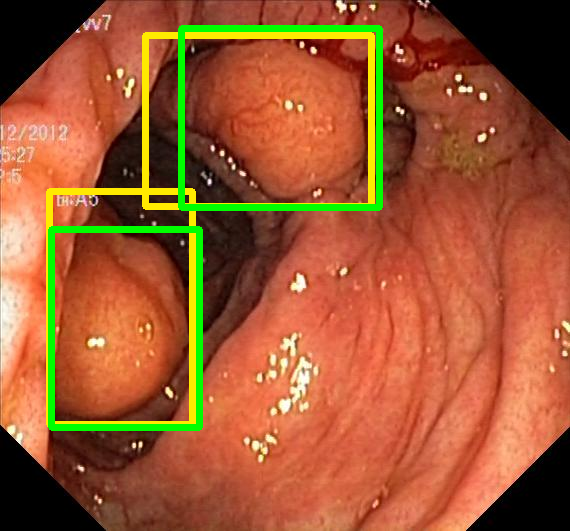

For all metrics, a higher value indicates better performance. The results for Kvasir-SEG are presented in Table VII and the results for CVC-ClinicDB are presented in Table VIII. Examples for Kvasir-SEG are shown in Fig. 2.

Input Target RN-HK-MC RN-HK-BT RN-IN-MC RN-IN-BT RN-IN-SL RN-NA-NA Refer to caption Refer to caption Refer to caption Refer to caption Refer to caption Refer to caption Refer to caption Refer to caption Refer to caption Refer to caption Refer to caption Refer to caption Refer to caption Refer to caption Refer to caption Refer to caption Input Target VT-HK-MC VT-HK-MA VT-IN-MC VT-IN-MA VT-IN-SL VT-NA-NA Refer to caption Refer to caption Refer to caption Refer to caption Refer to caption Refer to caption Refer to caption Refer to caption Refer to caption Refer to caption Refer to caption Refer to caption Refer to caption Refer to caption Refer to caption Refer to caption

Figure 2: Targets and predictions for two randomly selected instances of the Kvasir-SEG test set. For conciseness, we denote ResNet50s with RN, ViT-Bs with VT, Hyperkvasir-unlabelled with HK, ImageNet-1k with IN, MoCo v3 with MC, Barlow Twins with BT, MAE with MA, supervised pretraining with SL, and no pretraining with NA-NA.